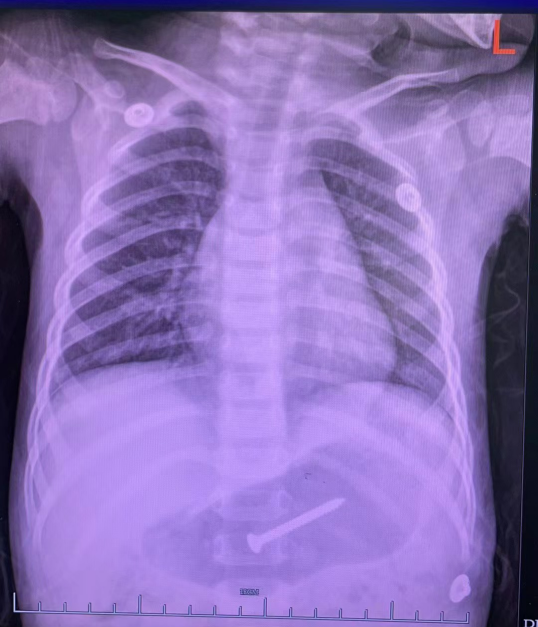

家长立即至浙大四院急诊儿科就诊,检查后发现胃区钉状致密影,螺丝钉随时可进入肠道、损伤肠道组织。

- 胸片显示异物位于胃腔内 -

危险性较大,经评估后,医生立即安排患儿入院,行急诊内镜下处理。